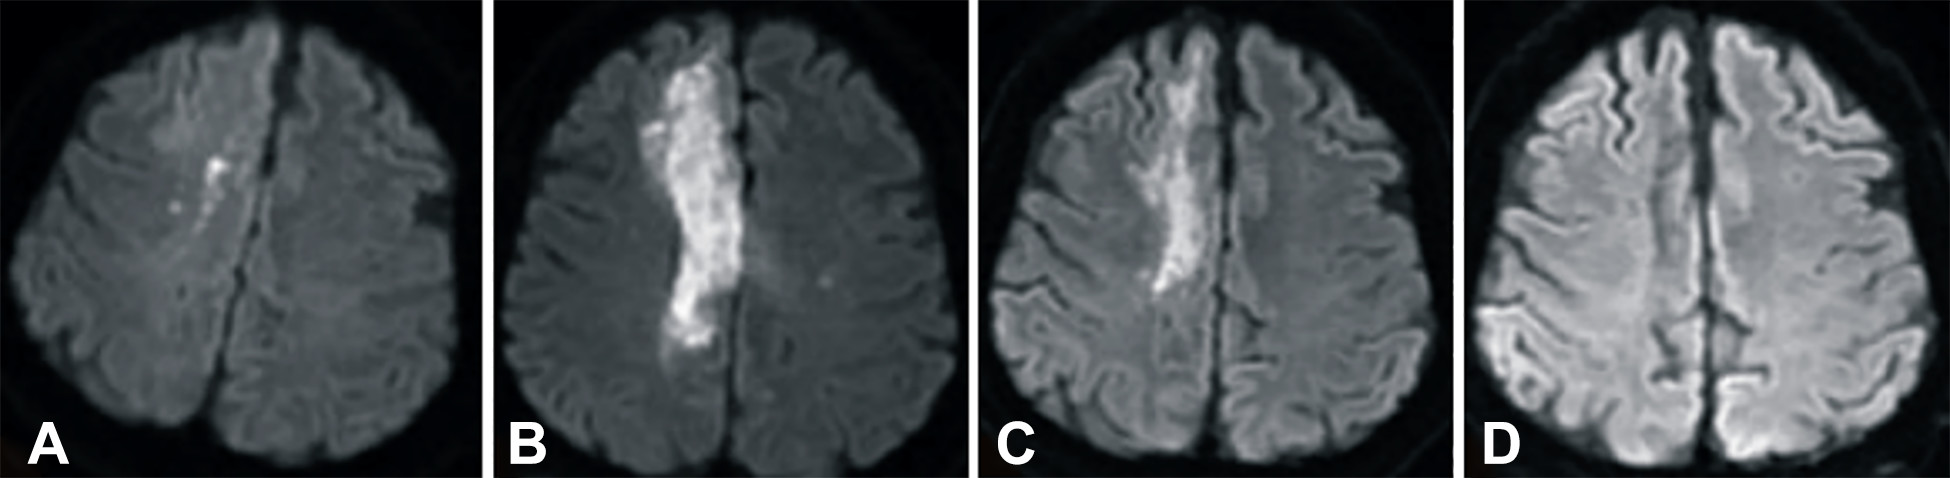

發(fā)病后2小時(shí)和8天行彌散加權(quán)成像(DWI)檢查,發(fā)現(xiàn)右側(cè)放射冠梗塞(白色信號(hào)增加),3個(gè)月后梗塞散在,6個(gè)月后消失(圖2A-D)。

卒中發(fā)病后2小時(shí)和單核細(xì)胞臍帶血輸注后6個(gè)月獲得的彌散加權(quán)圖像

圖2 . 卒中發(fā)病后2小時(shí)和單核細(xì)胞臍帶血輸注后6個(gè)月獲得的彌散加權(quán)圖像。(A)卒中后2小時(shí),(B)臍帶血輸注后1天,(C)臍帶血輸注后3 個(gè)月,(D)單核細(xì)胞輸注后6個(gè)月